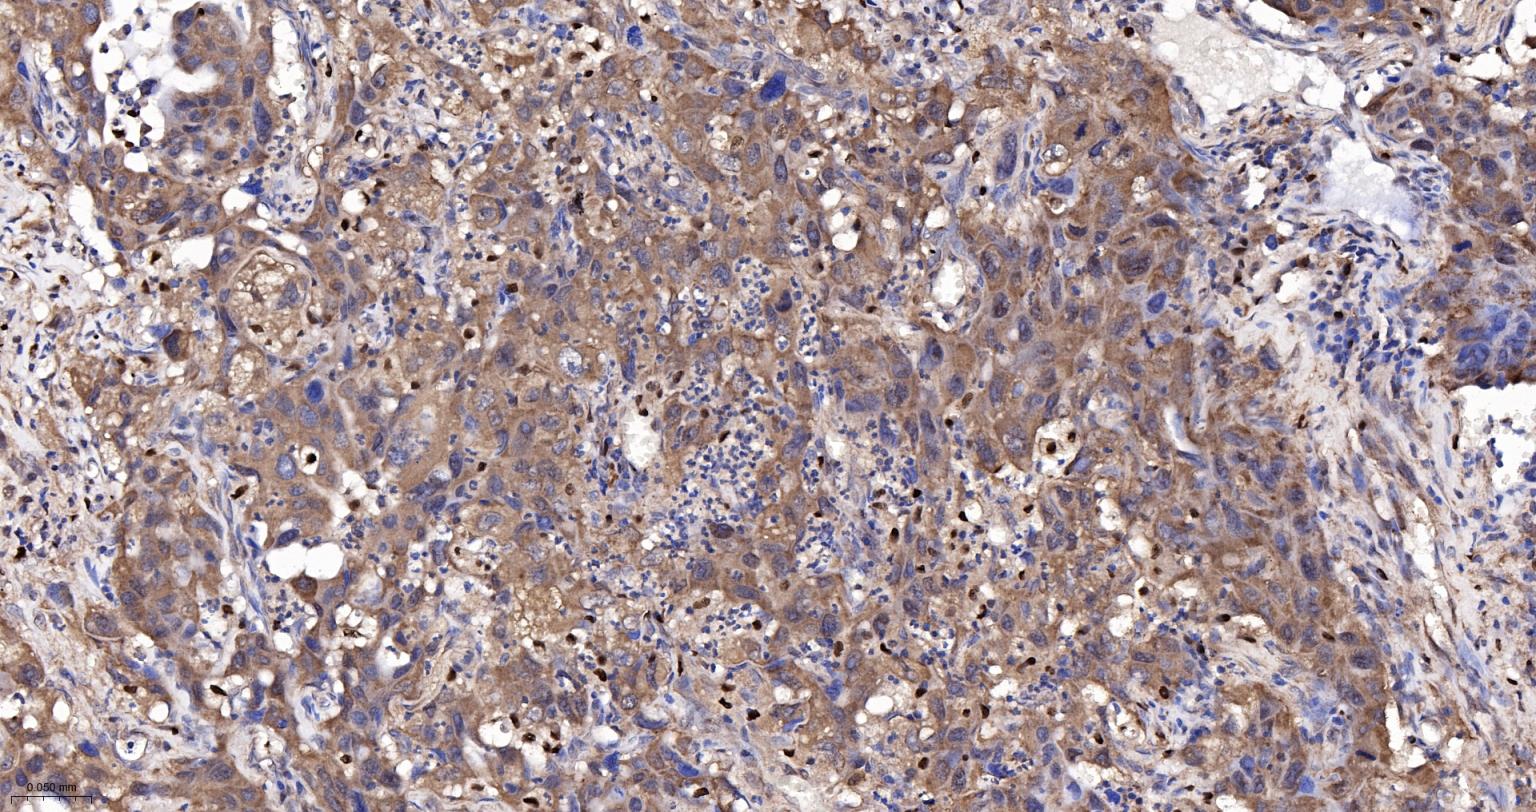

Paraformaldehyde-fixed, paraffin embedded Human Lung Cancer; Antigen retrieval by boiling in sodium citrate buffer (pH6.0) for 15 min; The section was incubated with UCHL3 Monoclonal Antibody, Unconjugated (bsm-63011R) at 1:200 overnight at 4°C, followed by conjugation to the bs-0295G-HRP and DAB (C-0010) staining.